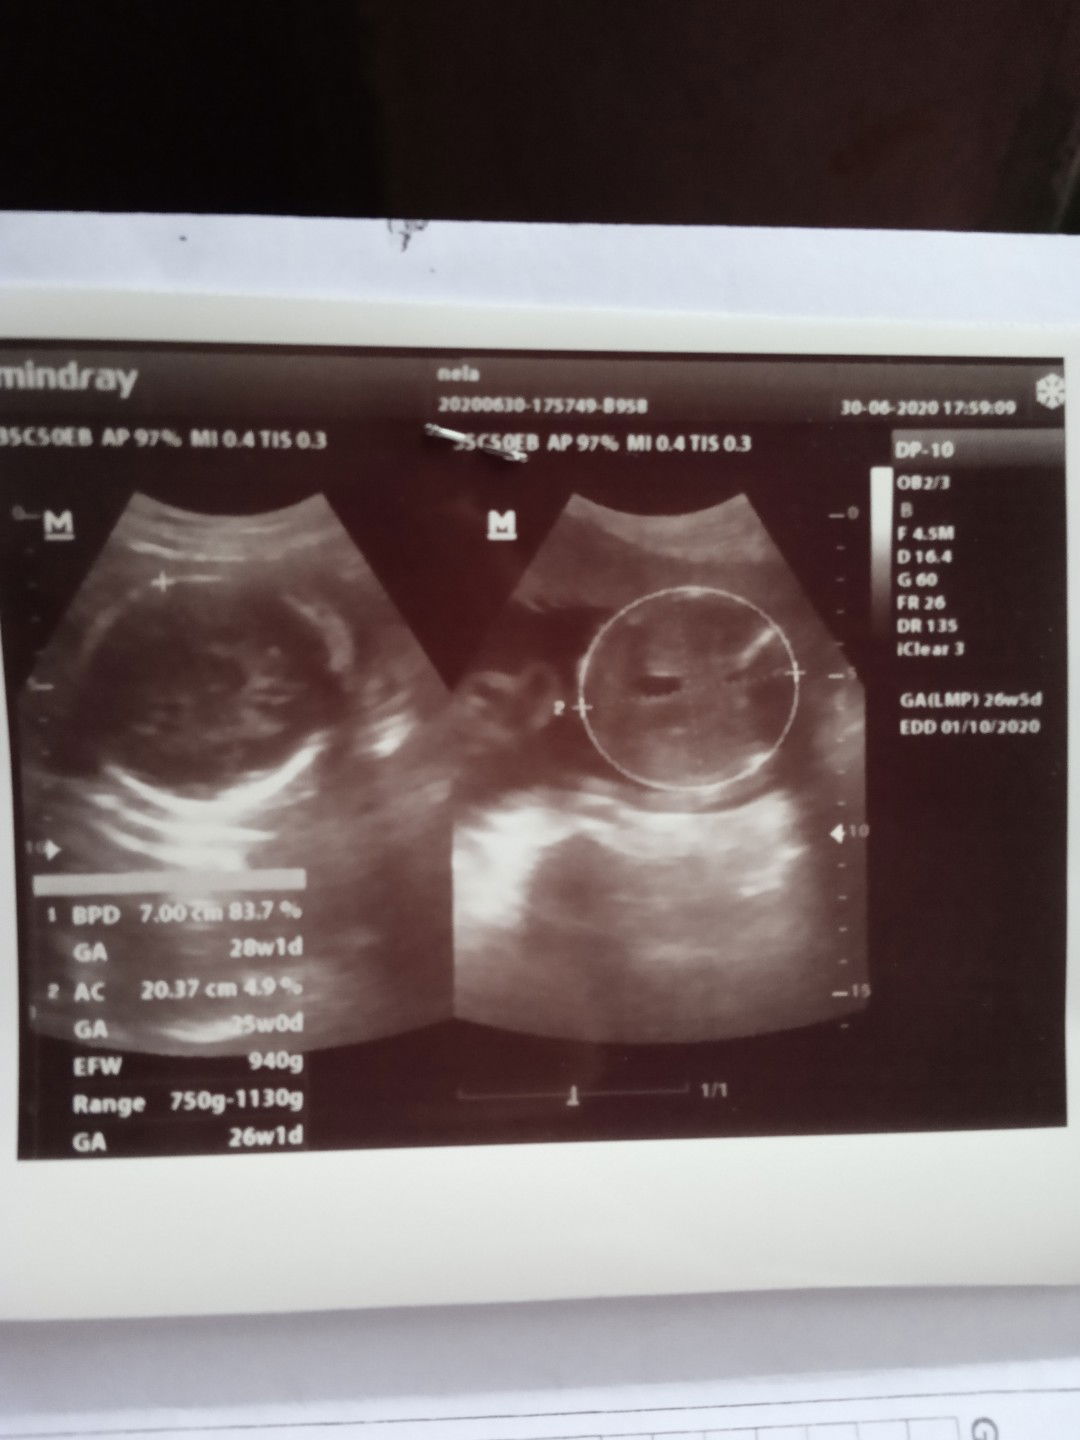

berat janin

Mau tanya bun usia kehamilan 26w3d di usg beratnya 940 gr normalkah? Soalnya perut masih kelihatan kecil...